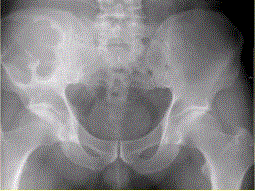

患者男,28岁,右下腹及臀部疼痛5个月余。查体:右髂骨外后侧压痛,右下腹可触及一软组织包块,质韧,固定。行骨盆正位CR、骨盆CT及MR扫描见下图。...

问题 患者男,28岁,右下腹及臀部疼痛5个月余。查体:右髂骨外后侧压痛,右下腹可触及一软组织包块,质韧,固定。行骨盆正位CR、骨盆CT及MR扫描见下图。 对于此病变的征象,描述不正确的是

选项 A.右髂骨翼分叶状溶骨性骨质破坏,边缘清晰硬化,形成巨大软组织肿块 B.右髂骨软组织肿块侵犯右侧腰大肌 C.右髂骨软组织肿块推压右侧腰大肌 D.T2WI示病灶内多发囊状高信号影 E.病灶内可见多发T1、T2均呈低信号的条状影,提示为纤维分隔